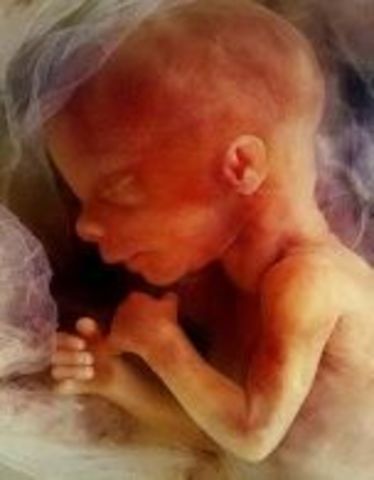

the fetus finishes developing its facial profial and finishes developing its vocal chords. the fetus' brain is fuly formed and it feels pain, its pancreas will begin making insulin and the fetus will such on its fingers.

Fact: the fetus will cry silently occasionally in its mothers womb, the fetus has reached 2.5 inches and weighs 0.7 ounces